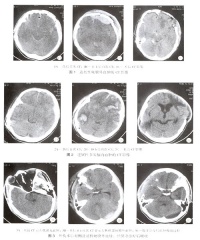

多发脑挫裂伤

双颞叶脑挫裂伤

对脑挫裂伤与脑震荡可以作出明确的鉴别诊断,并能清楚地显示脑挫裂伤的部位、程度和有无继发损害,如出血和水肿情况。同时,可根据脑室和脑池的大小、形态和移位的情况间接估计颅内压的高低。尤为重要的是,对一些不典型的病例,可以通过定期CT扫描,动态地观察脑水肿的演变或迟发性血肿的发生。近年来,在有此设备的医院CT已作为急性头伤的常规检查,因为单靠伤史和查体难以作出超早期诊断。Stein等(1990)指出在GCS13~15危害较小的轻型头

伤中,首次CT的阳性发现率竟占18%,并有5%需行手术治疗,强调早期CT检查的必要性。